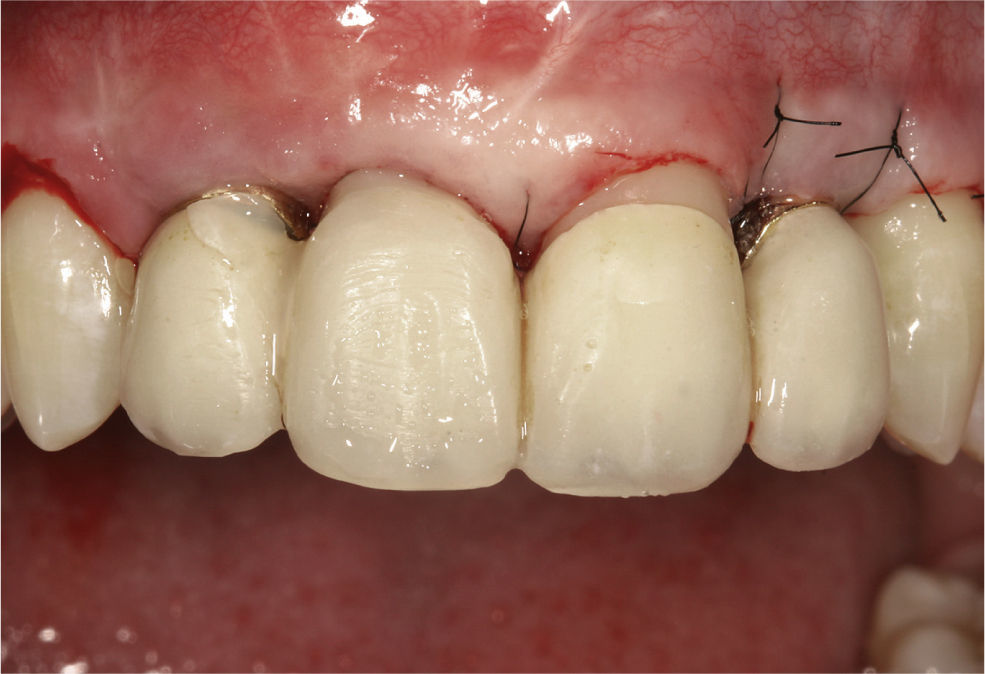

Con objeto de cubrir la dehiscencia residual e incre-mentar el volumen del tejido se practicó al cabo de 3 me-ses otro aumento con dos injertos de tejido conjuntivo procedentes del lado derecho e izquierdo del paladar (figs. 7 a 9). Transcurridos otros 3 meses se expuso el implante 12 mediante un colgajo de desplazamiento y se realizó un nuevo aumento de tejido blando. Se preparó el diente 21 para la colocación de una prótesis provisional y se retiró el pilar antiguo del implante 22 (figs. 10 a 12). Se colocaron pilares nuevos individualizados y angula-dos, fabricados con una aleación de alto contenido en oro. También se colocó el puente provisional 12-22 fabrica-do en el laboratorio. Aunque se había logrado mejorar considerablemente el volumen del tejido blando y con-formar el asiento del póntico 11, persistió un déficit de la papila de los dientes 11-12 que no se logró corregir de forma notoria ni siquiera con un nuevo aumento local en esta zona.

En el marco de la reevaluación estética llevada a cabo en junio de 2008 se recortaron los bordes incisales de los incisivos centrales que, en relación con el labio infe, eran excesivamente largos (fig. 13). Con este proce-dimiento se allanó el camino para dar a los dientes ante-rosuperiores cuadrados una forma rectangular mediante técnicas resectivas. Se aprovechó el alargamiento coronario quirúrgico para armonizar el festón de tejido blan y duro en las regiones del 14 al 24 y para aplanar li-geramente las papilas (figs. 14 a 16).